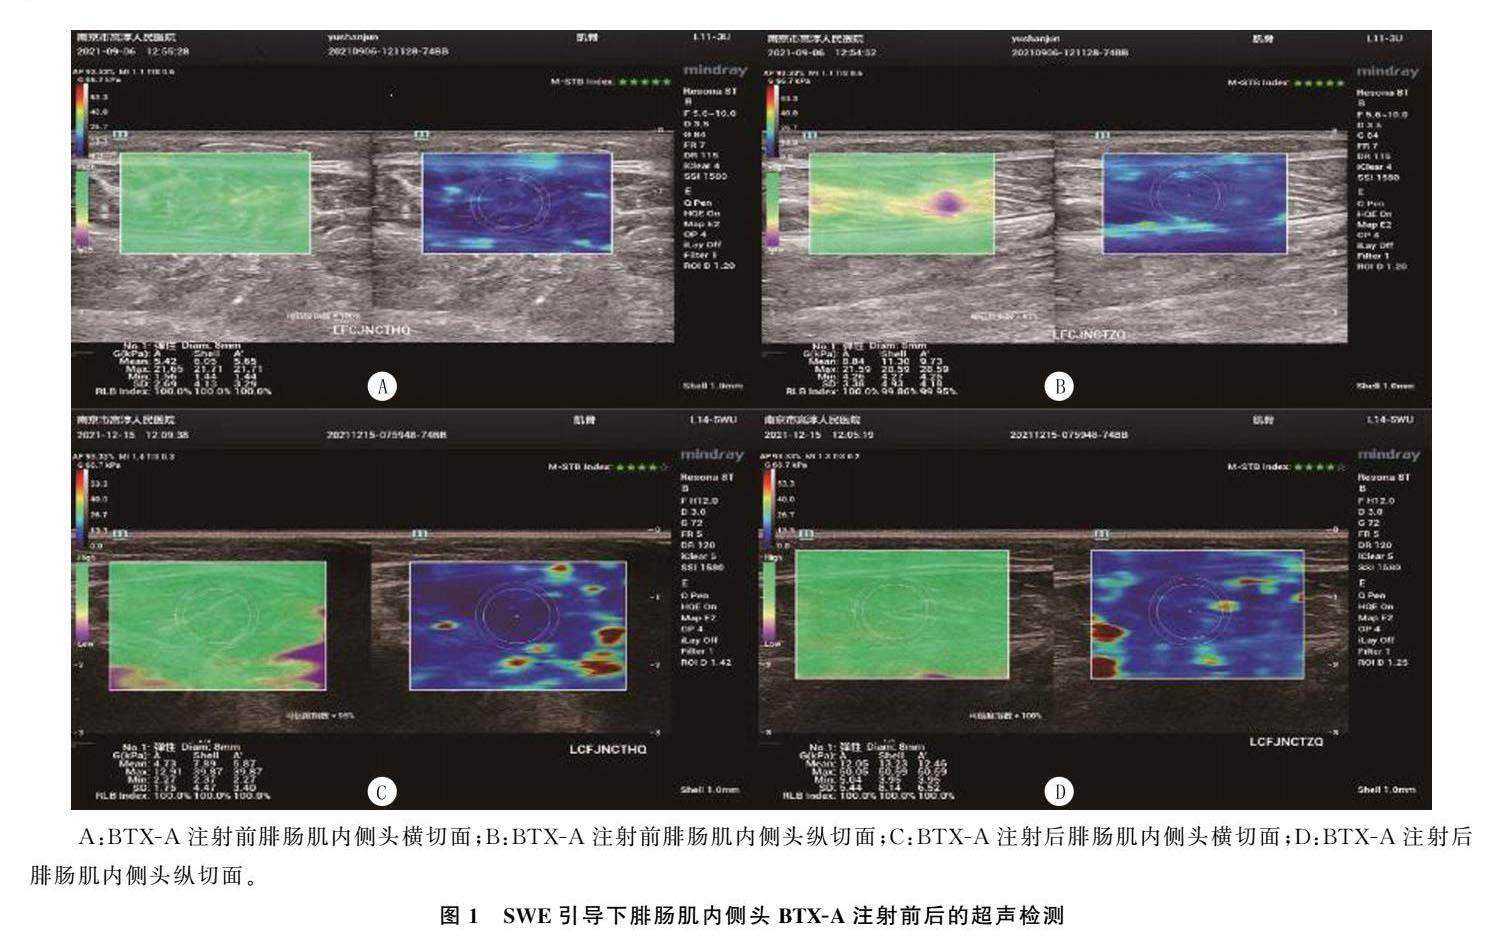

论著 | SWE下肌注BTXA联合综合康复训练治疗脑卒中下肢痉挛的效果

论著 | SWE下肌注BTXA联合综合康复训练治疗脑卒中下肢痉挛的效果